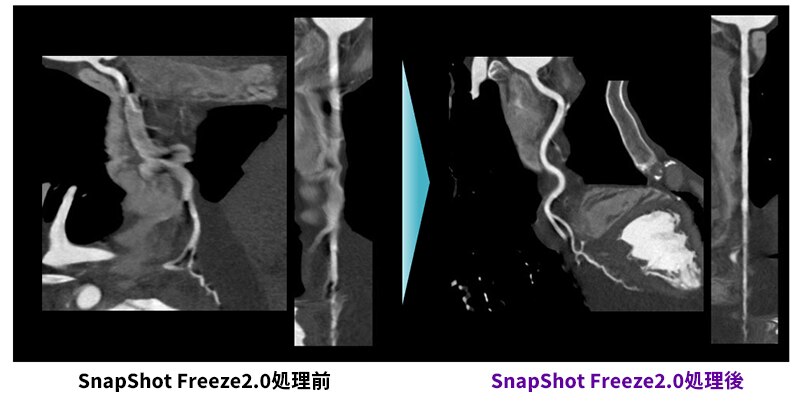

Revolution CTによる心臓CT・Dual Energy・高速撮影の臨床的メリット